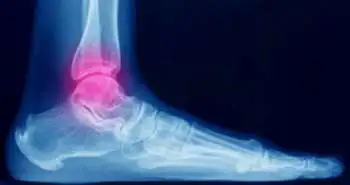

An update on the diagnostic techniques for ankle torque-related fractures

In traumatology, Ankle torque is the most commonly encountered injury mechanism. It mostly develops as an ankle sprain and often leads to an ankle fracture. The signs and symptoms are very unspecific on the differential diagnosis, and the conventional radiographs must be obtained to rectify it.  Ferràs-Tarragó J and investigators compared the ultrasound and standard X-ray images values found in ankle sprain-related fracture diagnoses. A total of 52 patients with ankle torque were considered for this 3-month prospective study. An ultrasound diagnosis was performed by the first researcher at their arrival to the emergency department (ED), mostly consisting of a longitudinal section of the fibula, tibia, and V metatarsal. A blinded independent investigator then carried out the usual diagnosis protocol via the traditional radiographs. The third independent investigator assessed the results when the required number was obtained. A Chi-squared test helped to contrast the outcomes between sensitivity, specificity, positive predictive value (PPV), and negative predictive value (NPV) distinguishing a non-inferiority hypothesis of our protocol against the standard X-ray images screening. On the detection of ankle torque-related fractures, echography portrayed to be at least as good as the standard radiographs. Nearly 8% of fractures were misdiagnosed with plain radiography in these patients, which is as per the lower limit found in the bibliography. In the first ultrasound assessment, all the false negatives on radiographs were true positives. The average time for the ultrasound protocol was 42 seconds.

The investigators concluded," The use of echography could decrease the number of radiography performed when diagnosing these kinds of fractures, hence reducing the amount of radiation exposure and expediting the diagnostic process and also the "in situ diagnosis".